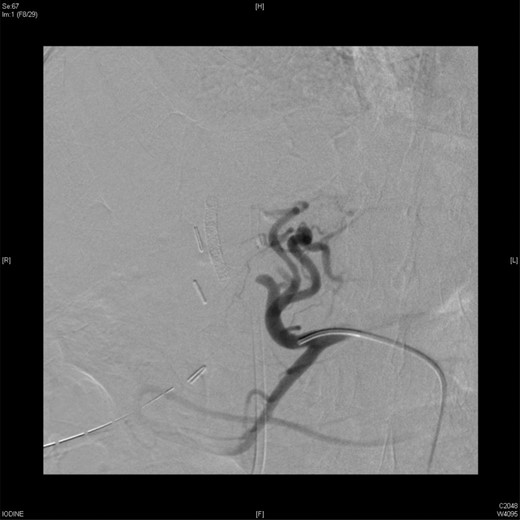

An angiographic scan showed superior mesenteric artery (straight arrow) and replaced right HAP (angulated arrow).